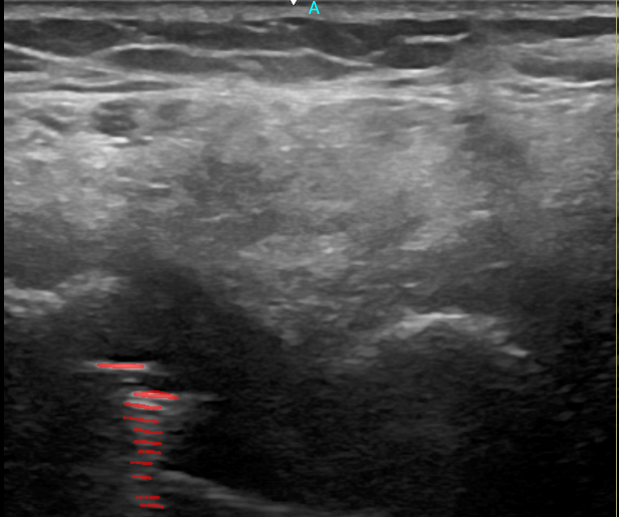

6. Artefacto de Anisotropía

La anisotropíaArtefacto común en ecografía músculo-esquelética que ocurre cuando el ángulo del haz de ultrasonido cambia con respecto a la estructura en estudio, resultando en una señal más débil cuando el haz no es perpendicular. es un artefacto común en ecografía músculo-esquelética y ocurre cuando el ángulo del haz de ultrasonido cambia con respecto a la estructura en estudio, como los tendones.

Mecanismo Físico

La señal reflejada depende del ángulo de incidencia:

• Cuando el haz no es perpendicular a la estructura, el eco retornado es más débil

• Produce una imagen más oscura que puede confundirse con patología

• Es especialmente relevante en la evaluación de tendones

Importancia Diagnóstica

Este artefacto tiene importantes implicaciones clínicas:

• Fundamental para evaluar la función de los tendones

• Permite evaluar el movimiento del tendón flexor del tercer dedo

• Ayuda a evitar diagnósticos erróneos

• Indica la necesidad de ajustar el ángulo de adquisición para obtener imágenes precisas

En la evaluación ecográfica, se pueden observar dos fenómenos importantes: la sombra acústica posteriorUna región oscura detrás de estructuras densas como el hueso debido a la atenuación del sonido. generada por el hueso, y el artefacto de anisotropíaLa apariencia variable de las estructuras según el ángulo de incidencia del ultrasonido..